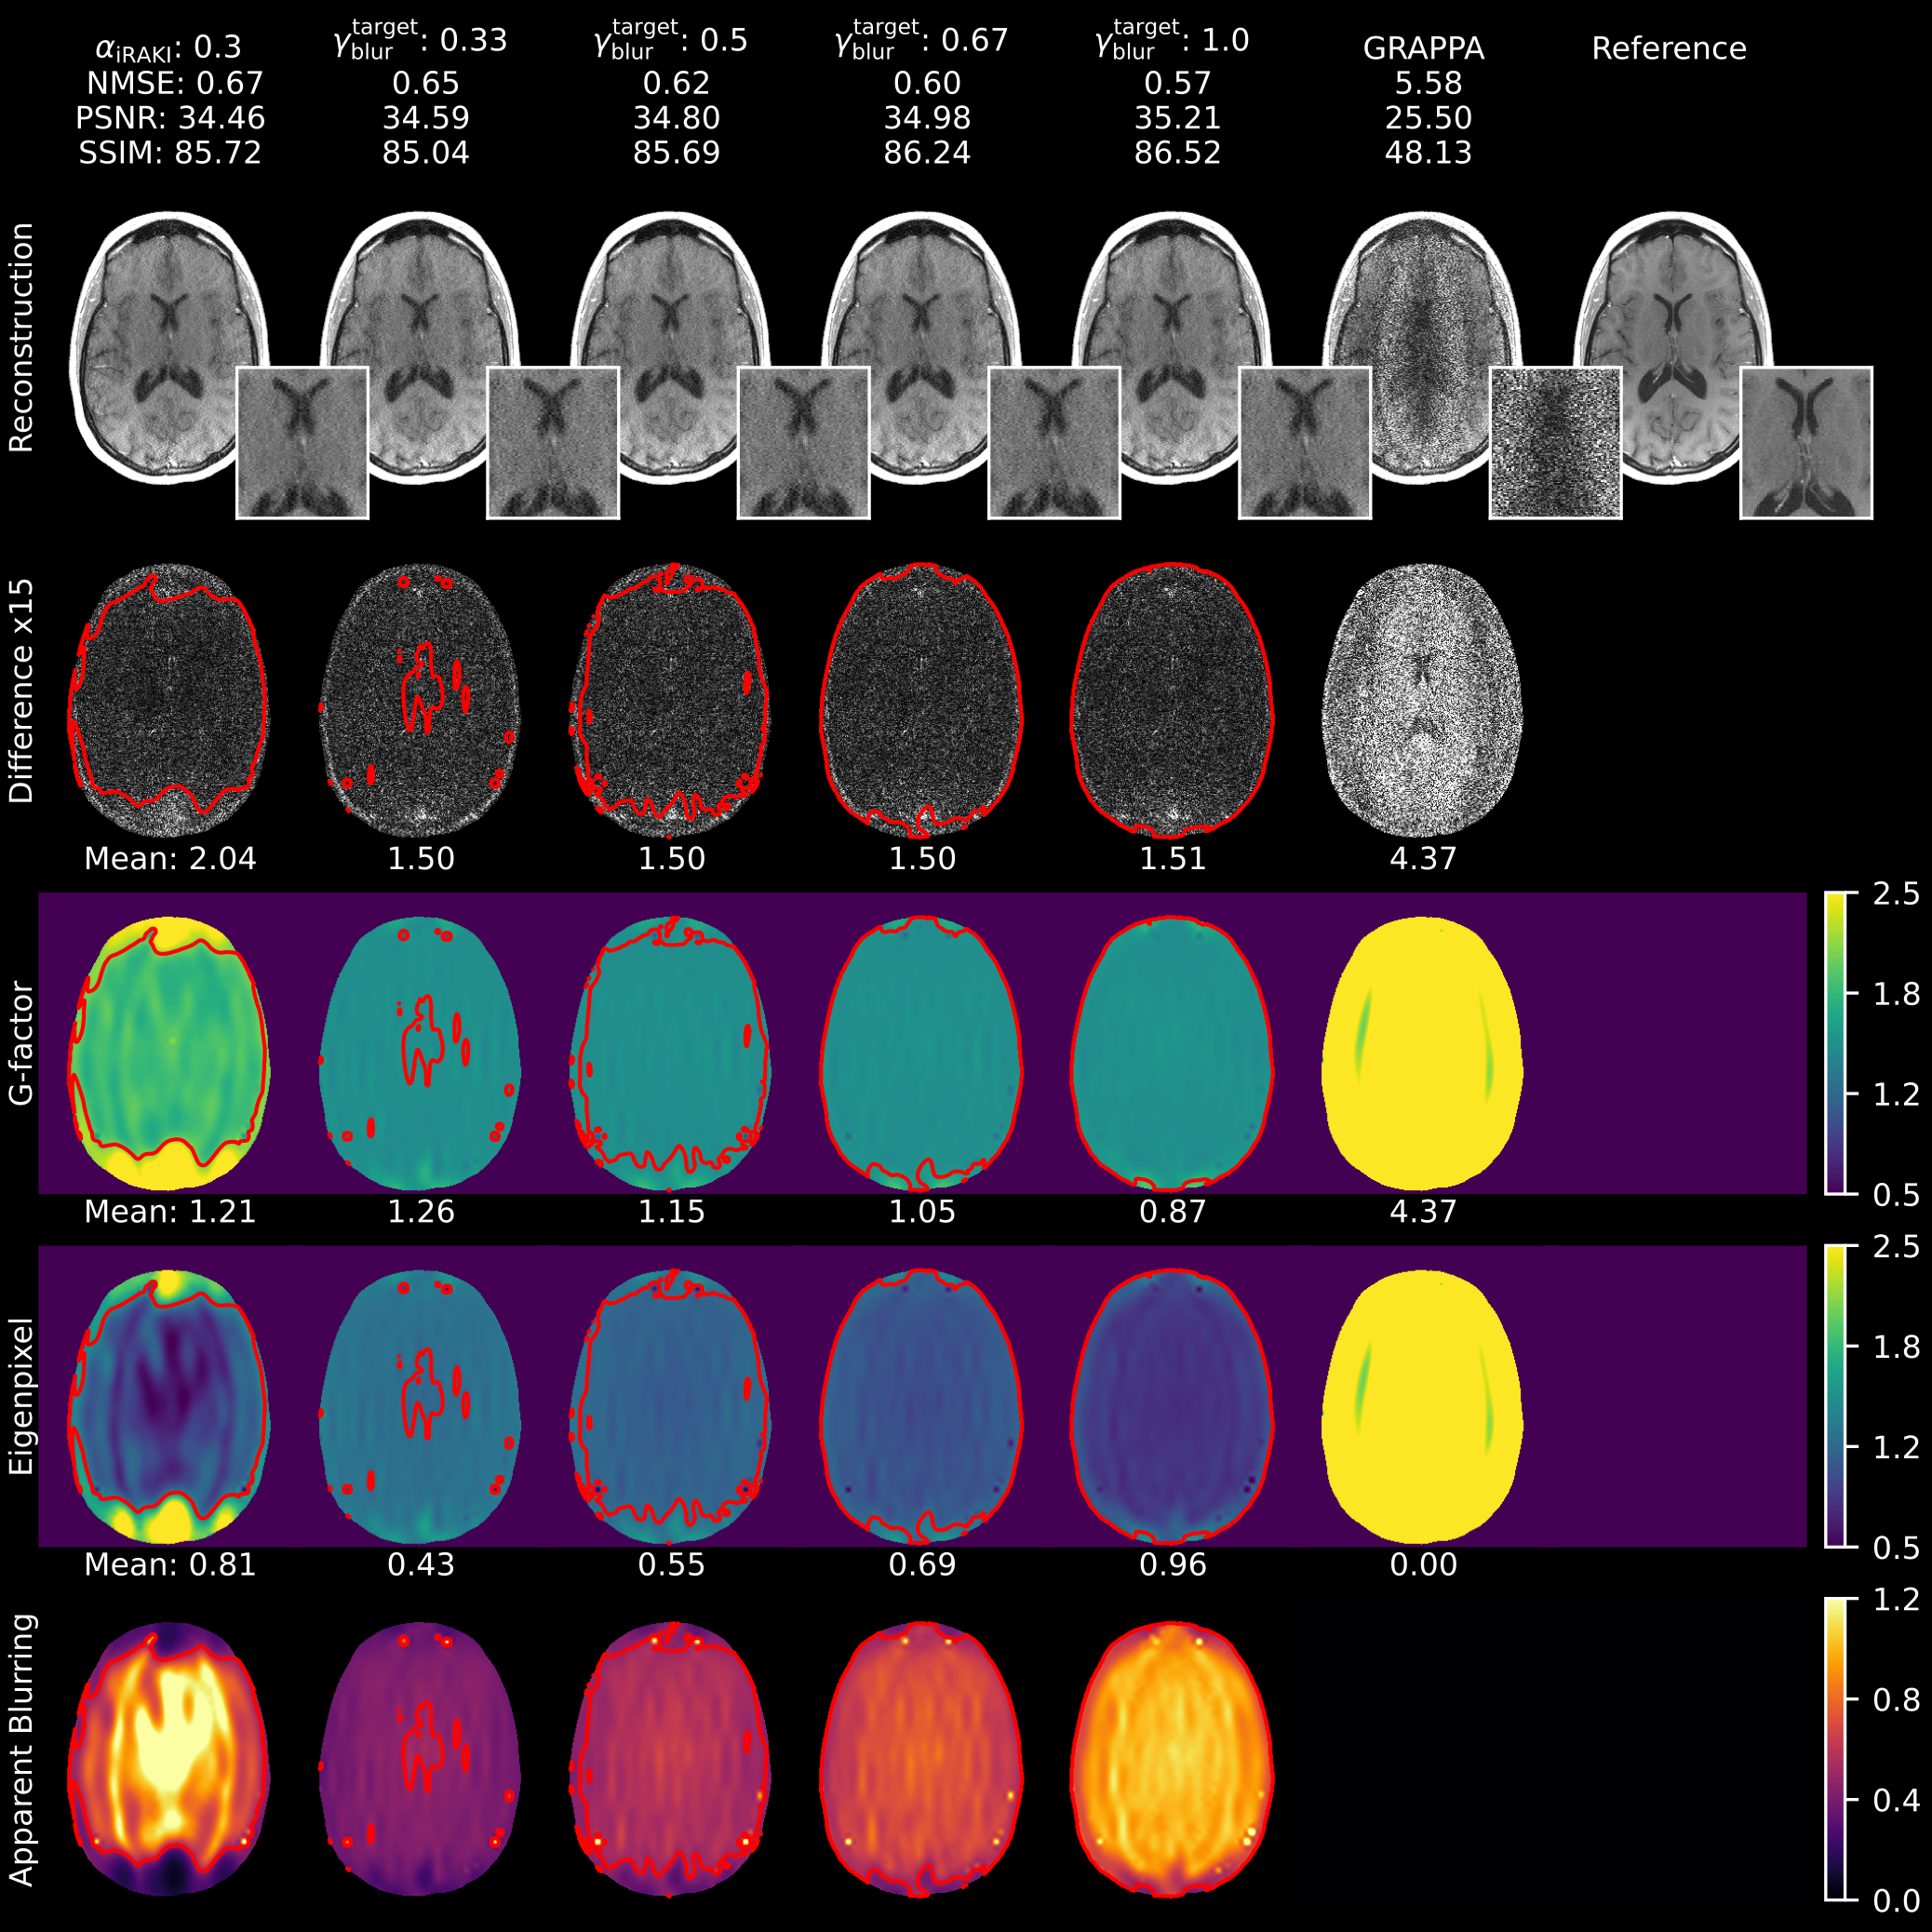

Figure 7 illustrates the impact of varying apparent blurring levels at a constant g-factor target for GIF-RAKI (R=5R=5). Compared to standard RAKI, GIF-RAKI variance regularization produces more homogeneous variance maps by eliminating spatially oscillating noisy and oversmoothed regions. While higher apparent blurring targets improve quantitative metrics, they also increase the perception of image smoothness. Under constant g-factor constraints, the loss function gfactor+blurG\mathcal{L}_{\text{gfactor+blur}}^{\scriptscriptstyle\text{G}} effectively shifts the balance between linear and nonlinear variance components. Similar performance is observed for GIF-iRAKI at a higher 6-fold acceleration (Figure 8). Supplementary Figures 1 and 2 demonstrate the effect of varying g-factor levels at a constant apparent blurring target for GIF-RAKI and GIF-iRAKI (R=5R=5), respectively. As the g-factor rises, increased pixel contamination is required to maintain a constant level of apparent blurring. Notably, apparent blurring remains dominant even at elevated g-factor levels.

While GIF-RAKI effectively mitigates Gaussian noise, it does not account for structured artifacts arising from insufficient training data (Supplementary Figures 3 and 4). iRAKI addresses these artifacts but introduces significant noise amplification, which is mitigated by GIF-iRAKI (Supplementary Figure 5). Supplementary Figures 6 and 7 detail the influence of input layer kernel dimensions [by(1),bx(1)][b_{y}^{(1)},b_{x}^{(1)}] on RAKI when abundant ACS data is available (R=6R=6, ACS=96\text{ACS}=96). A [2×5][2\times 5] kernel achieves robust denoising comparable to iterative approaches (Figure 8), while an expanded [4×7][4\times 7] kernel provides superior performance. To achieve high quality metrics, RAKI heavily relies on signal mixing manifesting as blurring hotspots.

Variance regularization beneficially influences image quality. Minimizing the g-factor imposes an absolute constraint on the overall noise level, while the apparent blurring regularization balances the ratio between linear and nonlinear components within the total variance (Figure 7 and 8, Supplementary Figure 1 and 2). These observations justify a regularization strategy that prioritizes achieving specific apparent blurring targets at lower g-factor levels. For the joint g-factor-apparent blurring loss gfactor+blurG\mathcal{L}_{\text{gfactor+blur}}^{\scriptscriptstyle\text{G}} specifically, targets of γgfactortarget=1.25\gamma_{\mathrm{gfactor}}^{\mathrm{target}}=1.25 and γblurtarget=0.5\gamma_{\mathrm{blur}}^{\mathrm{target}}=0.5 were proved to be effective for conservative variance regularization at the group level as well (Figure 10). The higher apparent blurring level imposed by variance regularization translated into elevated SSIM scores compared to RAKI. This indicates the metric’s inherent bias toward image smoothness, as previously documented Mason et al. [2020-04], Pambrun and Noumeir [2015]. Furthermore, gfactor+blurG\mathcal{L}_{\text{gfactor+blur}}^{\scriptscriptstyle\text{G}} encourages homogeneous variance maps and prevents the eigenpixel variance from dropping below one, thus avoiding non-physical scenarios. Simultaneously, it suppresses the network’s tendency to replace noisy regions with nonlinear signal mixing from other pixel locations, thereby reducing the central blurring hotspots (Figure 9).